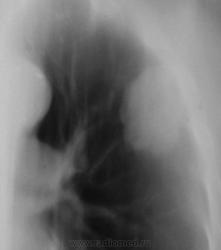

Зацепили при расшифровке флюорограмм, какие будут мнения уважаемые коллеги?

Была произведена обзорная рентгенограмма, было рекомендовано полное клиническое обследование, в плане проведения д/диагностики рекомендована также консультация фтизиатра.

Но, видать основания для тревоги не было. И, через год пациент был направлен на профилактическую флюорографию.

Пацинт стандартно был дообследован.

Однозначно была рекомендована консультация онколога.

Но..., прошел год и пациент был направлен на профилактическую флюорографию органов грудной клетки....

Пациент находился в терапевтическом отделении по поводу другого, не лёгочного заболевания, был выписан, и лечащий врач, окончательно просматривая историю болезни заметил, что в текущем году пациент не проходил профилактической флюорографии и направил на "флюшку", на которую пациент явился на следующий день после выписки.

Интересно то, что пациент, поступая в отделение, планово, по направлению поликлиники должен был на догоспитальном этапе пройти "флюшку", как и другие общеклинические анализы и необходимые исследования.

Стационарного (лечащего врача) волновало лишь одно, чтобы в историю болезни вклеить талон (квиточек), о прохождении профилактической флюорографии...